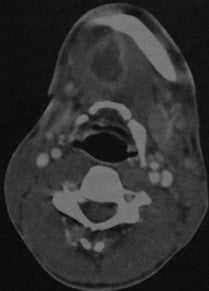

КТ с контрастированием: абсцесс дна полости рта справа с распространением под нижнюю челюсть. Абсцесс примыкает с правой стороны к телу нижней челюсти, определяется как образование со сниженной плотностью в центре, окруженное усиленной стенкой. Поднижнечелюстная железа смещена кзади (стенка абсцесса интактна, инфильтрация в данном случае отсутствует).

Абсцесс дна полости рта, расположенный справа около средней линии. КТ с контрастированием: объемное образование с типичным снижением плотности в центре, окруженное усиленной стенкой. Мелкий абсцесс слева, примыкающий к нервно- сосудистому пучку, с сопутствующим отеком поднижнечелюстных мягких тканей.